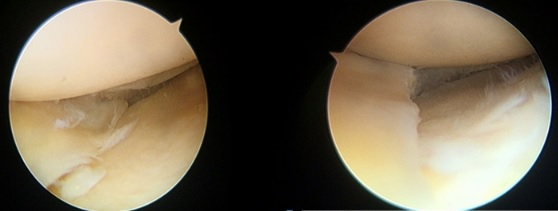

오히려 파열 위치에 따라서는 지속적으로 무릎을 사용하게 되면 파열 부위가 점점 커질 수 있어 파열의 크기가 크거나 파열이 진행될 가능성이 높은 위치라면 관절경을 이용한 수술적 치료를 시행하는 것이 표준 치료로 정립돼 있다.